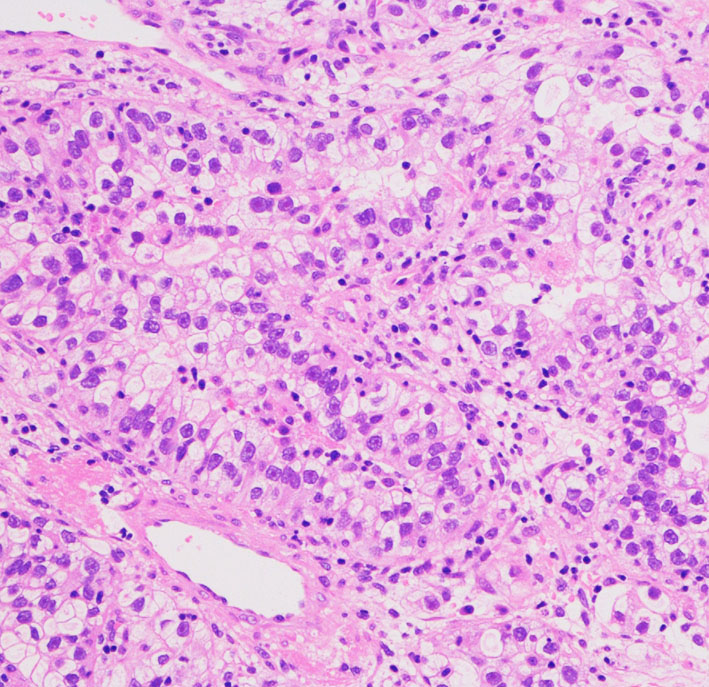

転移性脳腫瘍の手術と病理診断の意義

転移性脳腫瘍の摘出標本です。粘液産生もあり中分化型管状腺癌 tublar adenocarcinomaと診断されます。おそらく大腸癌からの転移ということは予想できますが,正確な臓器が解るわけではありません。かつては,病理診断をするために転移性脳腫瘍を生検することなどもありましたが,ペット PETなどの診断方法が発達した近年では,診断のための転移性脳腫瘍の手術がなされることはほとんどありません。